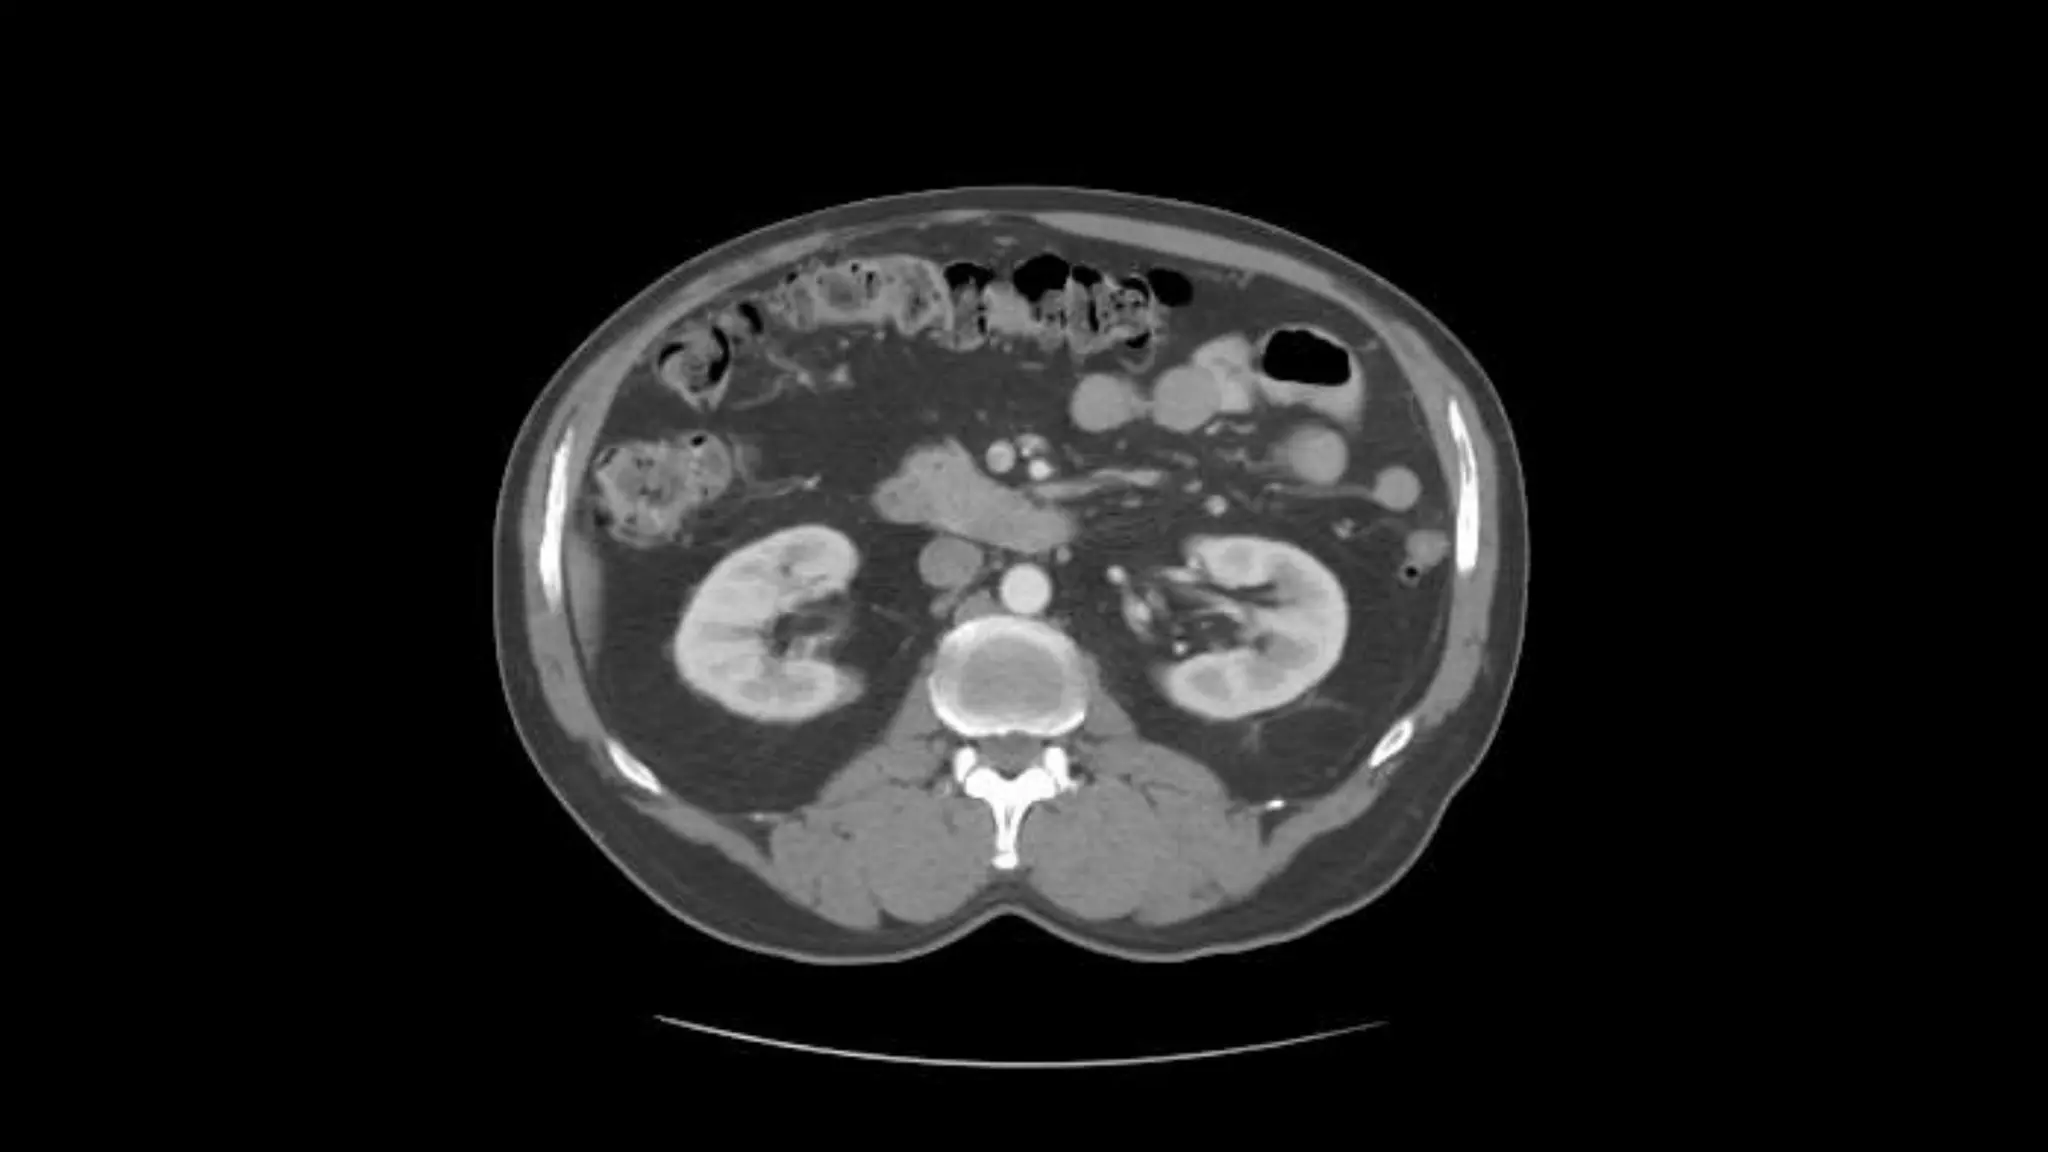

Here we see the right and left renal vein entering into the Inferior Vena Cava. We

Also see the left renal artery branching off the aorta and heading toward the left

kidney. Page up and down to trace these vessels.

Here we seethe right and left renal vein entering into the Inferior Vena Cava. We Also see the left renal artery branching off the aorta and heading toward the left kidney. Page up and down to trace these vessels.